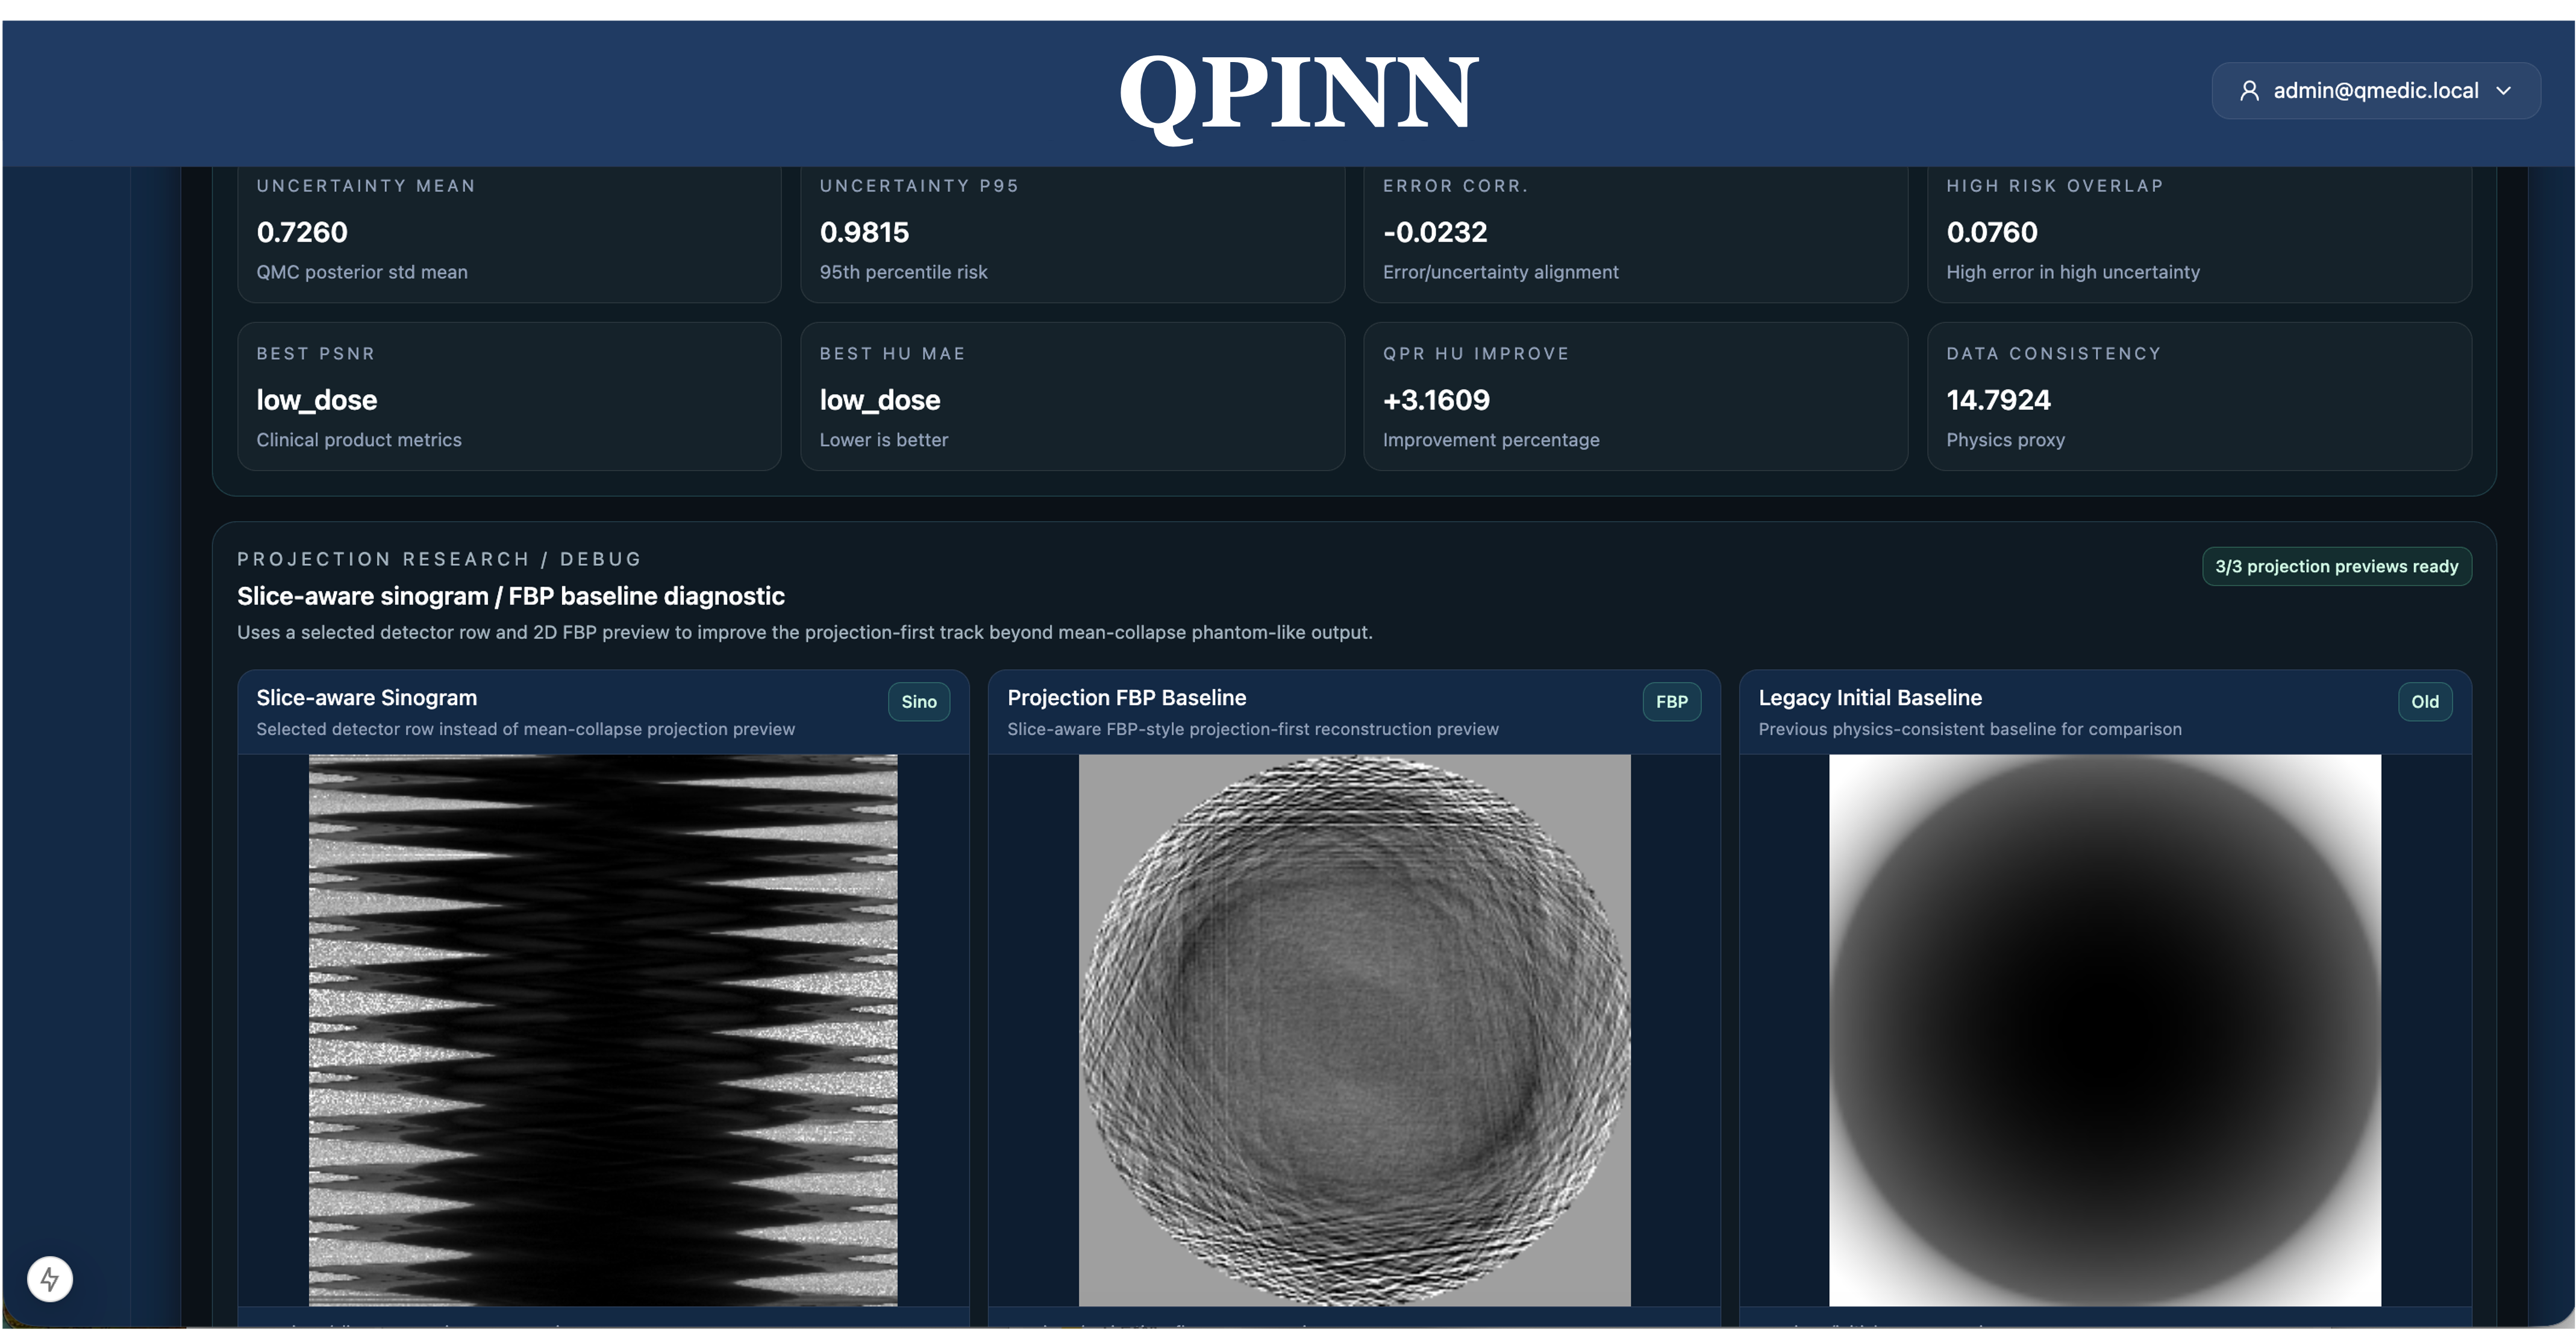

Physics-informed modeling for scientific computing, inverse problems, digital twins, and industrial optimization where domain constraints matter as much as raw AI output.

Lead commercial platform for CT/MRI-oriented reconstruction, QPR-assisted refinement, side-by-side comparison, and quality-governed imaging workflows.

The first commercial wedge is QMedic in CT and MRI reconstruction, refinement, comparison, and quality governance. The same platform can extend into digital twins, inverse problems, energy and wind-system optimization, and other HPC-intensive workflows where trust and traceability matter.

QPINN supports industrial and scientific domains where black-box AI is insufficient: inverse problems, wind and energy optimization, digital twins, manufacturing simulation, and other HPC-heavy workloads.

Research publication supporting QMedic’s imaging credibility and reinforcing SQK’s trust-centered product positioning.